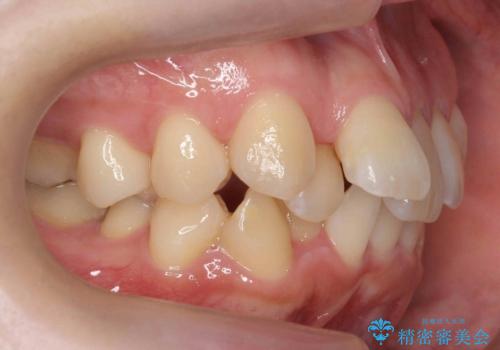

20代女性 受け口 手術をしなくても変わります

- 前歯の受け口を主訴に来院。

前歯の切端同士を合わせることはできますが、顎を前に出さないと咬めない状態でした。

下の小臼歯を2本抜歯しています。

上顎の両側7番は後から生えてきています。